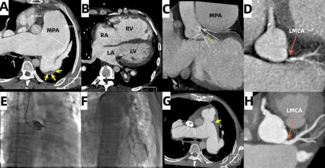

Ka-chun Un, MBBS, MRes; Cheung-chi Lam, MBBS; Hay-son Chen, MBBS; Chun-ka Wong, MBBS; Ho-on Alston Conrad Chiu, MBBS; Yui-ming Lam, MBBS; Kwong-yue Eric Chan, MBBS

A 36-year-old man with unrepaired double inlet and double outlet right ventricle, severe pulmonary stenosis, and dextroversion, who was on the heart transplant waiting list, presented with acute heart failure.